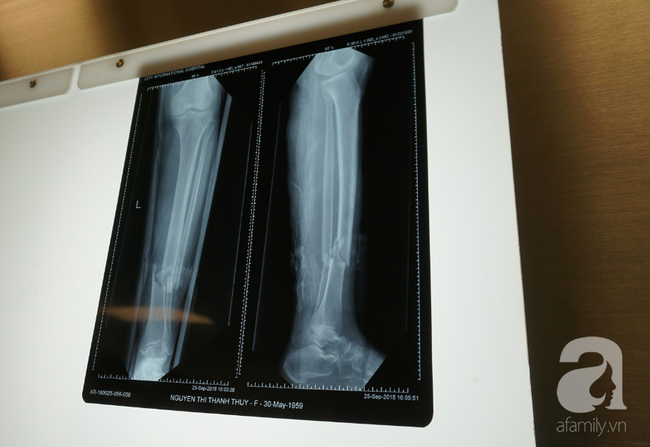

29/09/2018 02:35Nhất quyết không cho truyền máu người lạ, người phụ nữ ở TP.HCM suýt mất chân vì nhiều bệnh viện từ chối mổ

Ngày 28/9, Bệnh viện (BV) Quốc tế City cho biết, nơi đây đã thực hiện thành công ca mổ kết hợp hai xương cẳng chân cho một nữ bệnh nhân bị gãy chân do tai nạn nhưng lại đưa ra yêu cầu hết sức "kỳ lạ".

Trước đó 4 ngày, bà Thủy (59 tuổi, ngụ ở TPHCM) bị gãy xương chân trái do tai nạn giao thông. Sau khi nhập viện và làm các xét nghiệm tiền phẫu, BS chẩn đoán bệnh nhân bị gãy hở 1/3 dưới hai xương cẳng chân trái, xương chày gãy chéo có mảnh rời, xương mác gãy ngang mức xương chày. Các cơ chày trước, mác bên dập nát, mô dưới da dập nát nhiều.

BS Trần Văn Bé Bảy, Khoa Chấn thương chỉnh hình của BV cho biết, bệnh nhân bị gãy hở hai xương cẳng chân rất nặng. Nếu không phẫu thuật can thiệp kịp thời, bệnh nhân có thể dẫn đến diễn biến xấu.

Thậm chí sẽ gặp những biến chứng nguy hiểm như: tổn thương mạch - thần kinh, hội chứng chèn ép khoang, nhiễm khuẩn, cẳng chân sưng nề, đoạn chi.

"Ca phẫu thuật kéo dài 1 giờ đồng hồ. Các BS tiến hành phẫu thuật cắt lọc mép da và mô dưới da dập nát, nắn xương chày kết hợp bằng nẹp, dùng kim xuyên trong lòng tủy cố định xương mác với kiểm tra C-arm đinh vào ống tủy" - Thành viên kíp mổ chia sẻ.